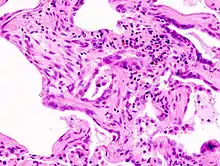

Micrograph of usual interstitial pneumonia (UIP). UIP is the most common pattern of idiopathic interstitial pneumonia (a type of interstitial lung disease) and usually represents idiopathic pulmonary fibrosis. H&E stain. Autopsy specimen.